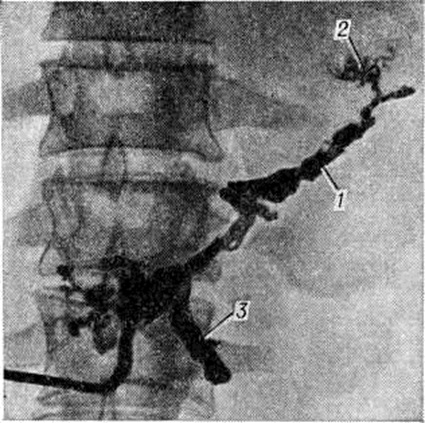

Рентгенодиагностика. При рентгенологическое исследовании желудочно-кишечные тракта обнаруживают в случае увеличения поджелудочной железы смещение желудка кверху и кпереди, расширение дуоденальной петли и уплощение медиального контура нисходящей части двенадцатиперстной кишки (рисунок 1). С помощью релаксационной дуоденографии (смотри полный свод знаний: Дуоденография релаксационная) на этом контуре можно выявить короткие ригидные участки, ряд заострённых углублений в виде игл (спикул), вдавления по краям большого сосочка двенадцатиперстной кишки. На обзорных снимках поджелудочной железы определяют также камни или отложения солей кальция (рисунок 2), а на компьютерных томограммах обнаруживают расширенный и деформированный проток поджелудочной железы. При холеграфии (смотри полный свод знаний) иногда находят сужение дистального отдела общего желчного протока.

Рис. 2.

Рентгенограмма области поджелудочной железы: множественные известковые камни по ходу протока поджелудочной железы.